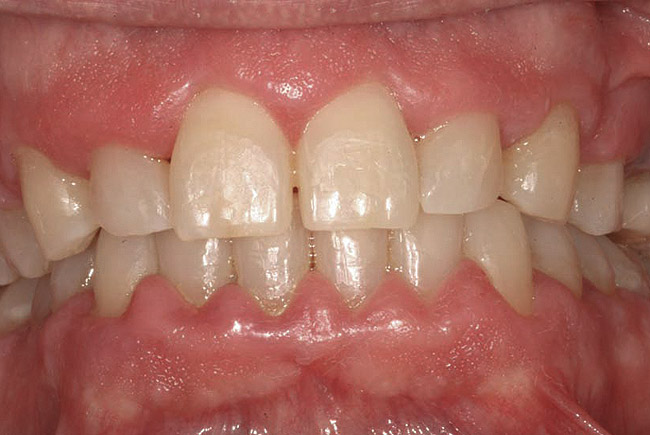

Fig 1. A 66-year-old male patient with multiple restorations, taking 100 mg Dilantin (phenytoin) daily for approximately 5 years. (photo courtesy of Asim Alsuwaiyan, BDS)

Figure 1

Drug-induced gingival enlargement is typically described as nodular, firm in consistency, and hard upon palpation. Clinical manifestations can be more severe in areas where local irritants such as plaque, defective restorations, and orthodontic or prosthetic appliances are present (Figure 1).7 Drug-induced gingival overgrowth is quite different between animals and humans. As demonstrated in rat models, the incidence of macroscopic gingival changes is usually close to 100% in all three of the previously mentioned classes of medication.8 In humans, however, the incidence has been reported to vary according to medication: 10% to 50% for phenytoin, 8% to 70% for cyclosporin-A, and 0.5% to 83% for nifedipine.6